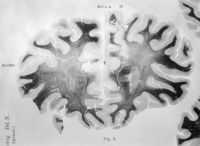

Image[Sans titre]